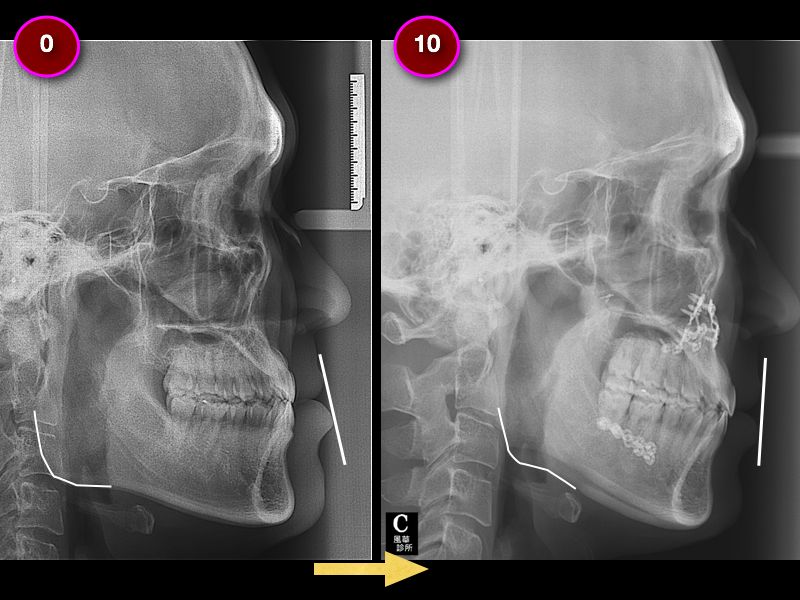

以X照可以明顯看出,

矯正前(左),厚道臉型很明顯。

矯正後(右),上唇與下唇有完美的垂直線。

歐先生還有進行削骨手術,讓原本的國字方臉變成了U臉型甚至小V臉型